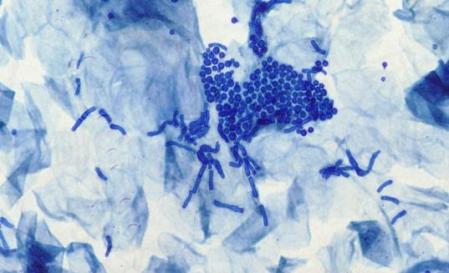

如果在高温潮湿、多脂多汗、营养不良和应用糖皮质激素等条件下,生活在皮肤表面的马拉色菌可能会由孢子形态转成致病性菌丝形态,侵犯皮肤角质层,导致花斑癣的发生;

(显微镜下花斑癣皮损处的孢子和菌丝)

(图源uptodate)